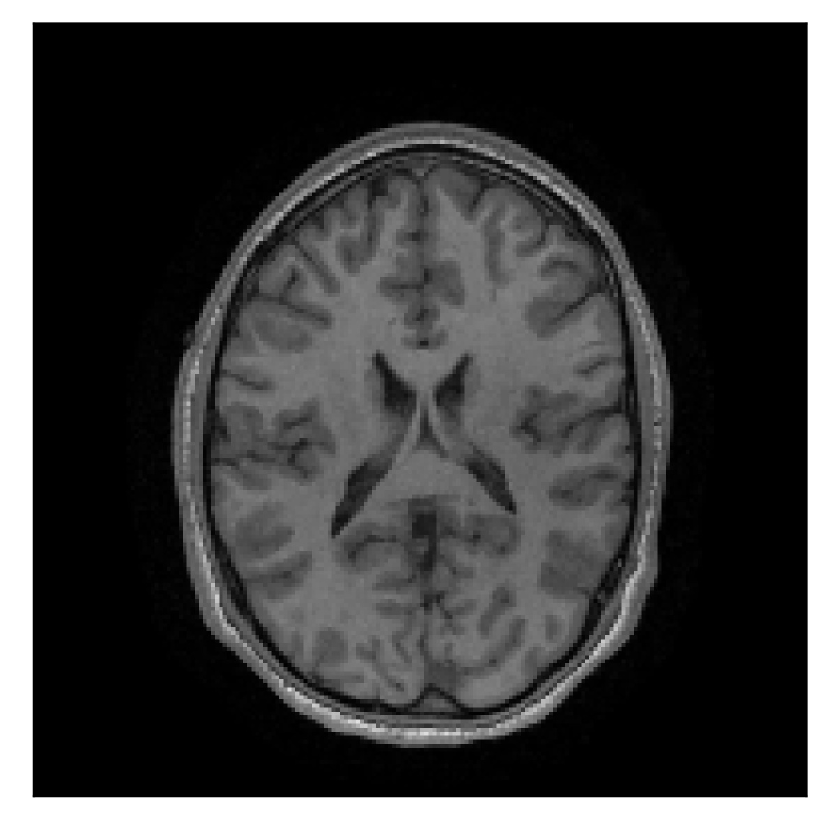

4.1 Experiment 1: robustness test

We gather the results for the robustness test described in Section 3.1 (volunteer 1) in Figures 2, 4, and 6 for motion corruption mechanisms associated to one, two, and five changes of position, respectively. Furthermore, we juxtapose the corrected images with varying degrees of corruption in Figure 8. We observe that the proposed method consistently ameliorates the corrupted scan. The quality indexes based on PSNR and SSIM show only a modest decrease in correction quality as a function of motion complexity (Figure 8).

| Section 3.1, Figure 2 | Sagittal | 23.94 | 27.95 | 0.7068 | 0.7936 |

| Coronal | 26.66 | 29.82 | 0.7653 | 0.8332 | |

| Axial | 25.40 | 30.16 | 0.7616 | 0.8490 | |

| Section 3.1, Figure 2 | T2-FLAIR | Completely corrected | Some blurring | No additional artifacts | Good grey white matter differentiation |